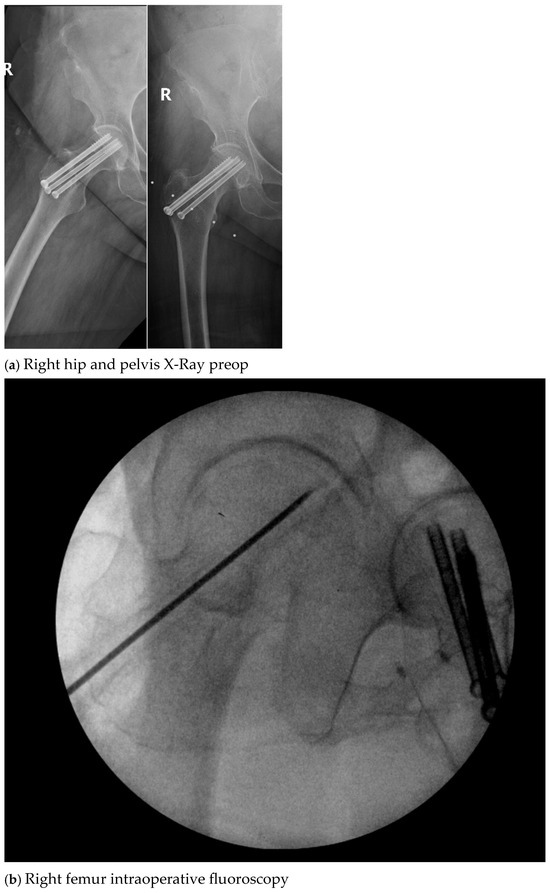

| 4. | 75 | F | Y | N | 20 | N | N | 17 | Right thigh and gluteal abscess with infected right femoral neck hardware and osteomyelitis |

| 9. | 37 | M | N | Y | 60 | 3.0 | N | 8 | Right femur osteomyelitis |